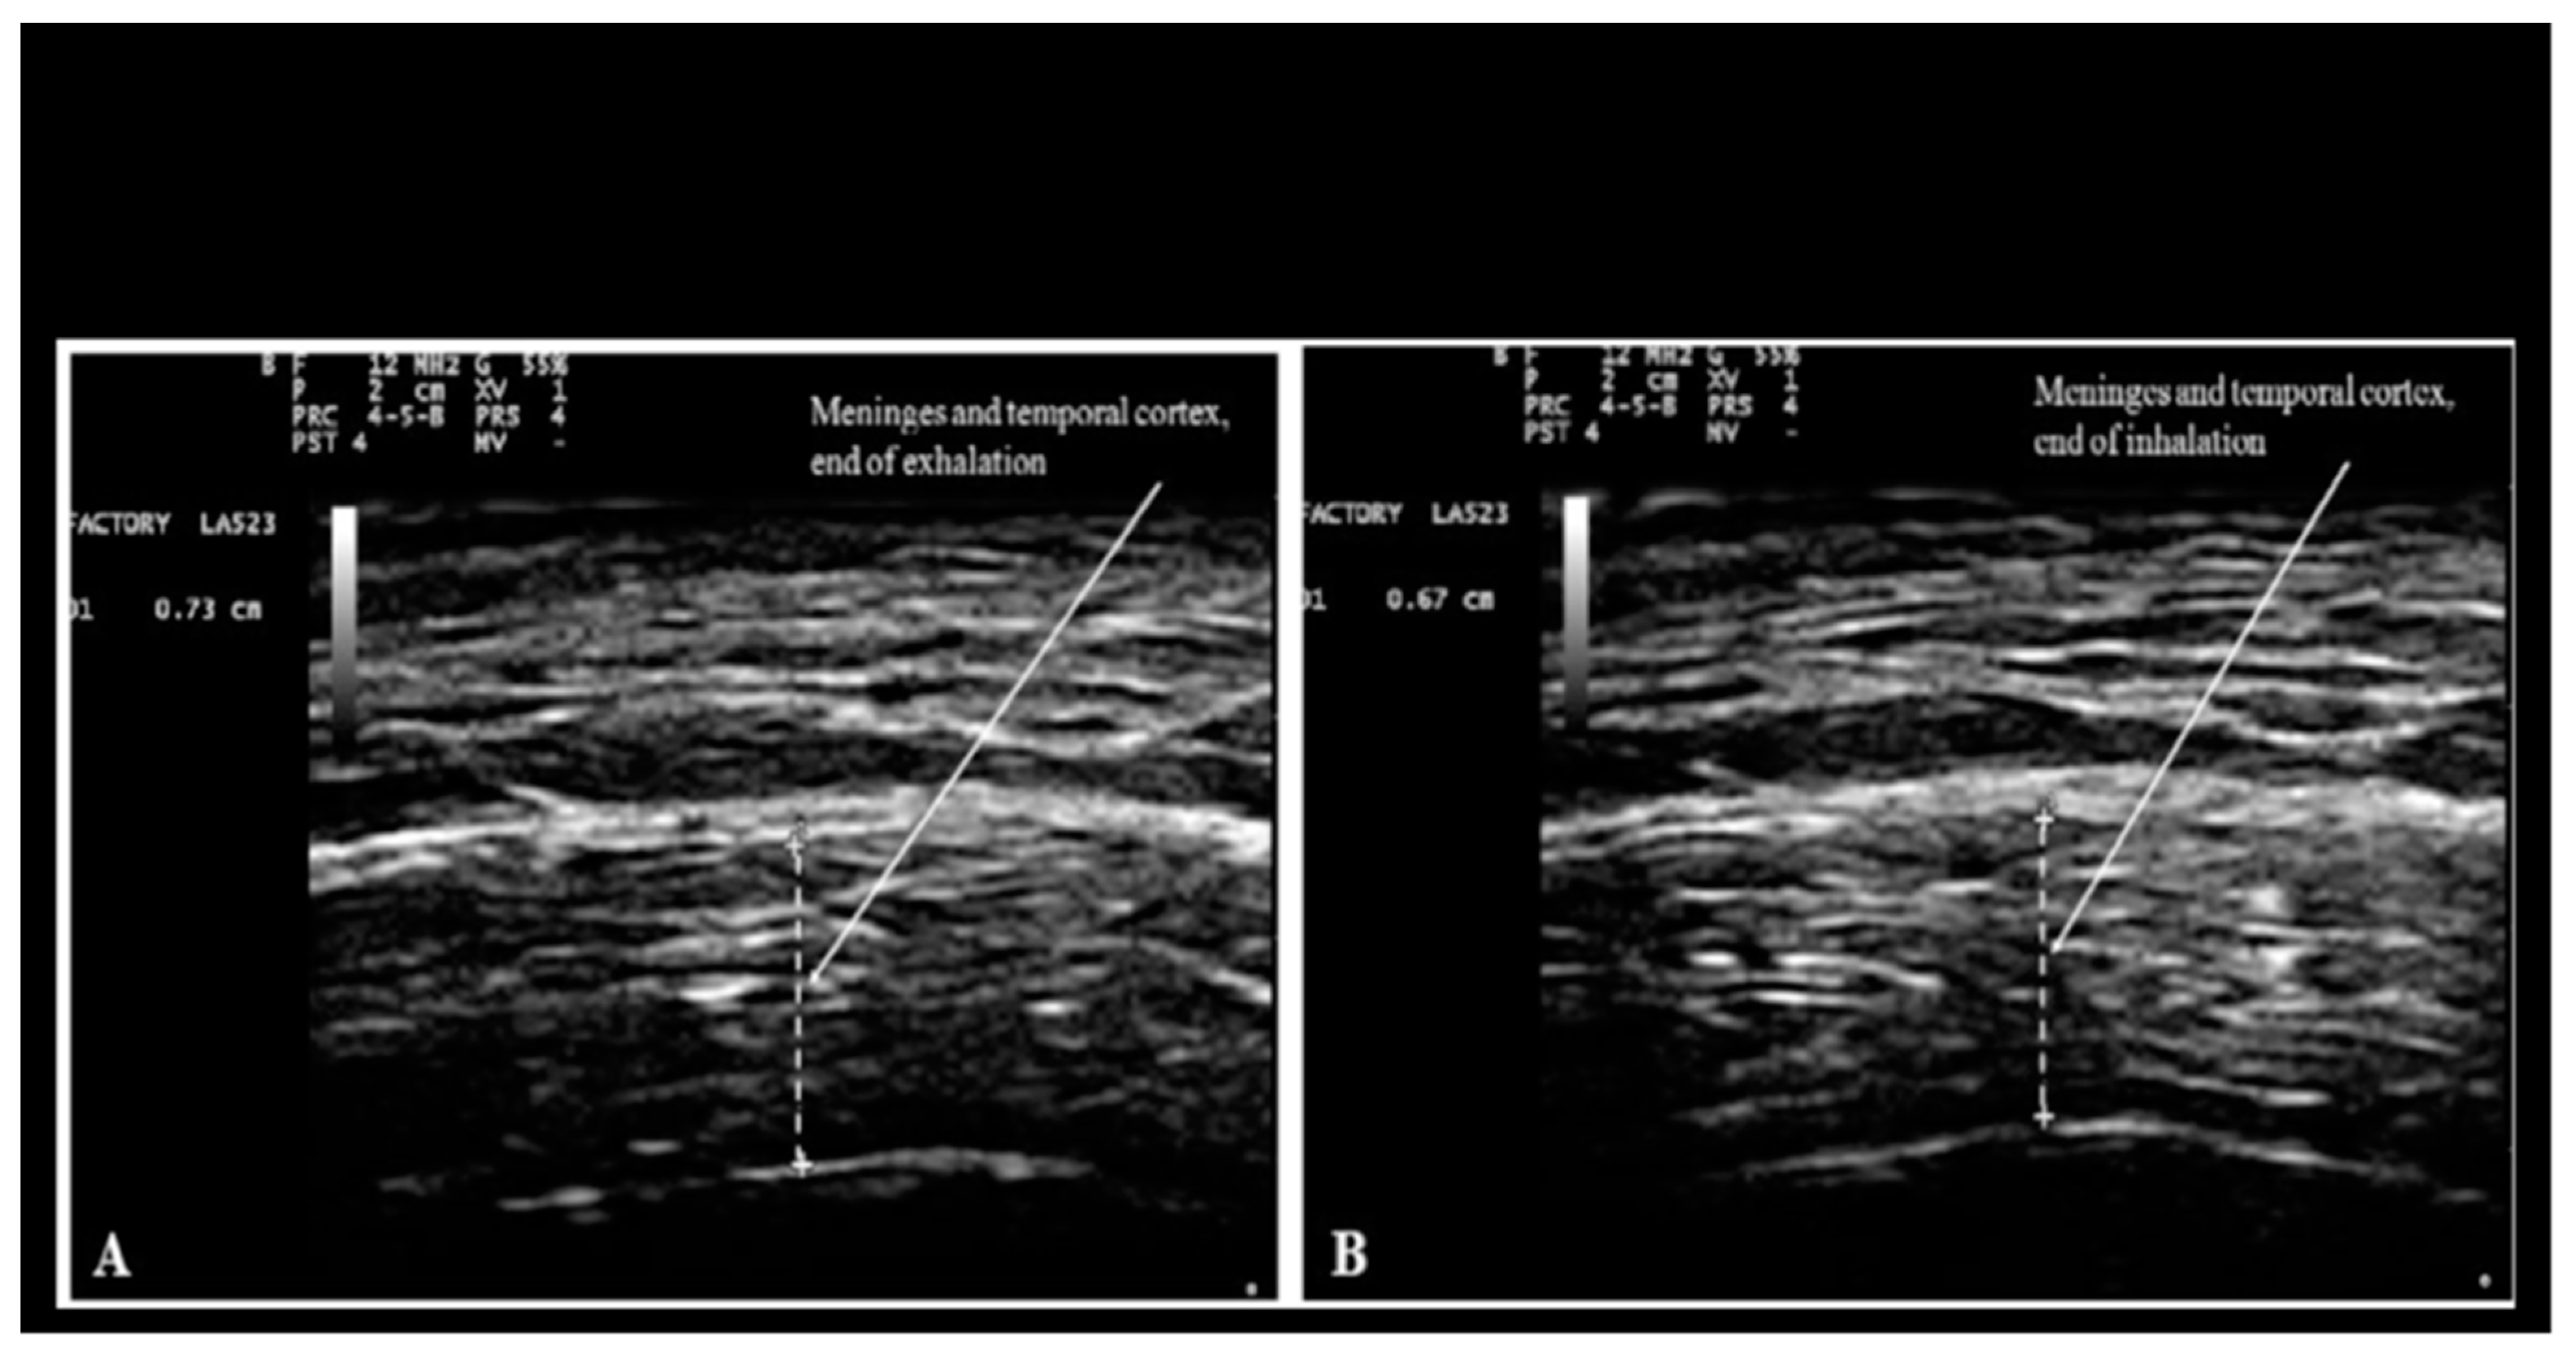

As far as the actual practice of Nichiren Daishonin's Buddhism is concerned, believers recite aloud (not silently) Nam-Myoho-Renge-Kyo for several minutes every day while performing a liturgy that is called Gongyo, a word originated in ancient China that can be translated as "assiduous practice". During chanting, believers keep their eyes open focusing on the object of worship as per the liturgy of Nichiren Shoshu. They typically repeat Nam-Myoho-Renge-Kyo approximately 15-20 times every breath with a frequency of approximately 3-4 respiratory cycles per minute with rapid inspirations and prolonged exhalations during chanting. Chanting Nam-Myoho-Renge-Kyo with a breathing pattern characterized by rapid inspirations and prolonged exhalations may have significant consequences on brain physiology at the light of the results reported by Dal Lin et al. (2021) and in the context of Orch OR. For example, it was demonstrated that the thickness and the water content of the brain cortex and the meninges vary with inspiration and exhalation; during exhalation, the thickness and the water content are greater (Ruggiero et al. 2013; Bradstreet et al. 2014; Ruggiero 2022).

Figure 11, reproduced below from Ruggiero et al. (2013), shows the changes of thickness and water content of brain cortex and meninges with inspiration and exhalation

Figure 11. Measurement of combined thickness of the meninges and the cortex of the temporal lobe at the end of forced voluntary exhalation (A: 7.3 mm), and inhalation (B: 6.7 mm). Reproduced from Fig. 5 of Ruggiero et al. (2014) under the terms and conditions of the Creative Commons Attribution 4.0 International Public License (CC-BY-4.0) license https://creativecommons.org/licenses/by/4.0/.